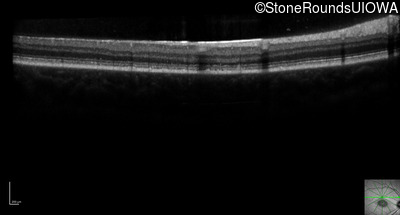

Optical Coherence Tomography - Right - 20/125 sc

Exemplar / OCT Stack